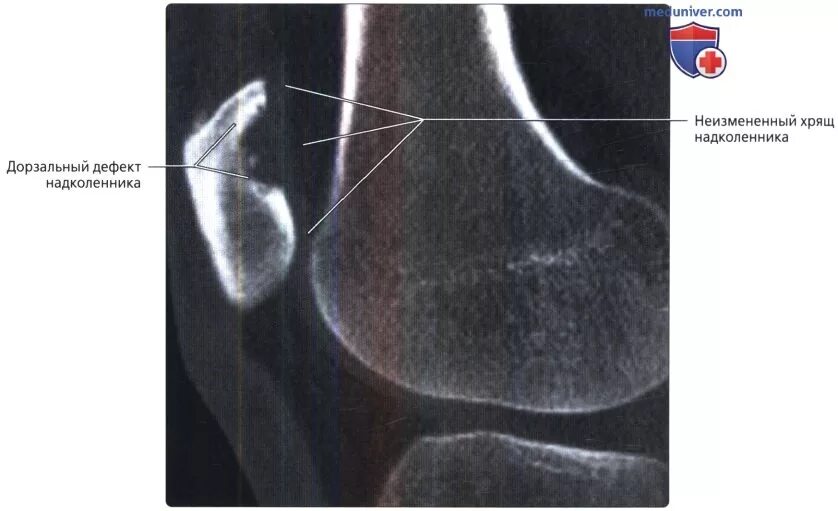

Повреждение хряща по outerbridge